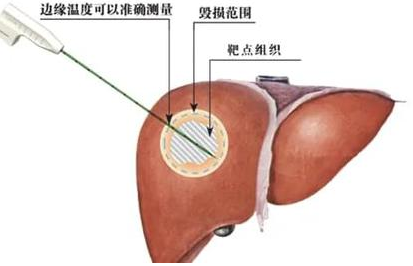

这是一封略显啰嗦的感谢信。但是唯有啰嗦才能详尽表达我的感激之情。非常感谢贵院普外二科主任张双卫先生及其医疗团队对我的诊治,正是贵院这群如张主任般杏林春暖的医生造福了故乡万千的病患。遥祝贵院高擒智慧之火炬,永筑健康之光芒,同时祝福张双卫主任及医院同仁阖家幸福,万事胜意。

山西省医师协会外科医师分会委员、山西省医师协会整合医学专委会委员、山西省医师协会肝癌专委会委员、山西省专家学者协会医学分会普外科专委会青年委员。